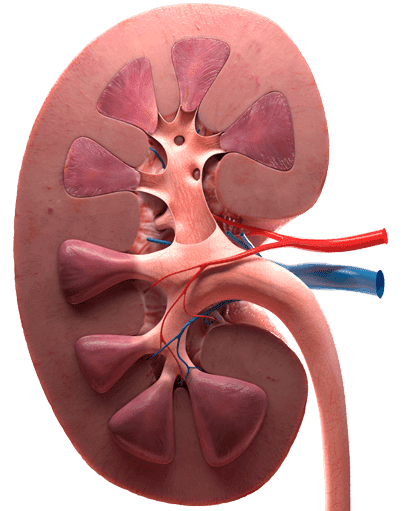

- Enfermedades en los riñones

- Litotripsia

- Endourología 3D HD

- Ultrasonografía